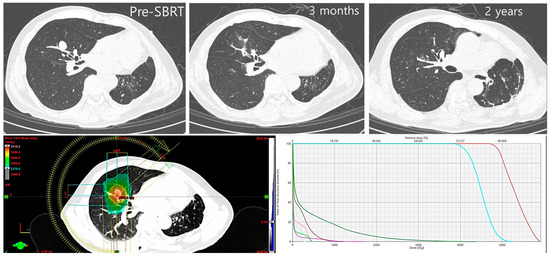

2. RT Applications